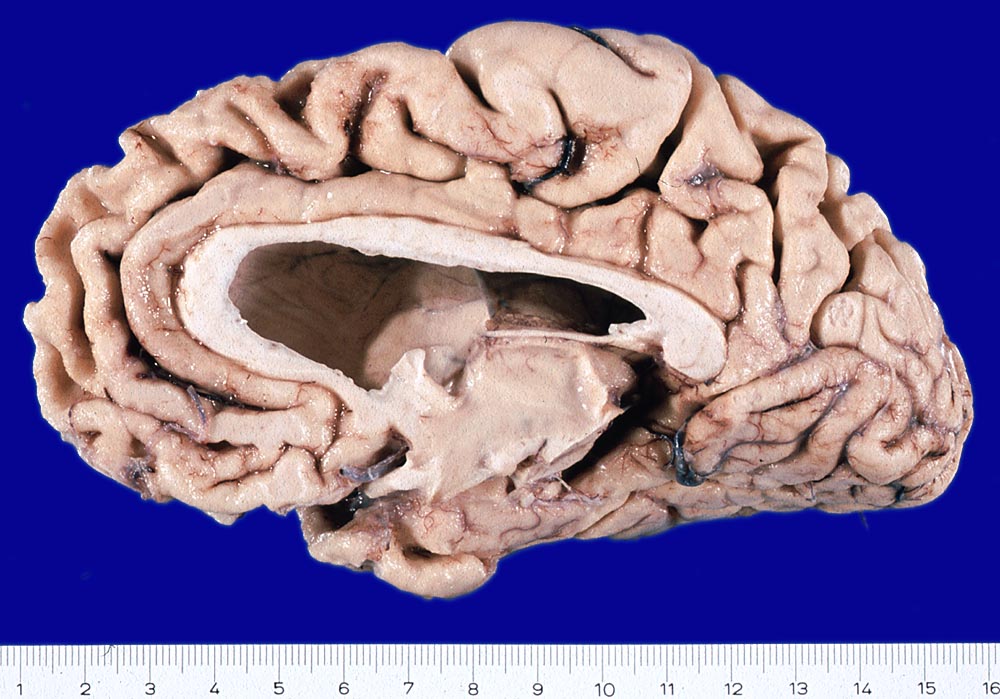

PathoPic ID 8373 - Morbus Alzheimer

Morbus Alzheimer

Hirn

Ausgeprägte Atrophie der Grosshirnrinde mit Verschmälerung der Gyri und konsekutiver Verbreiterung der Sulci sowie Erweiterung des Seitenventrikels.

Demenz

Makroskopie

83

männlich